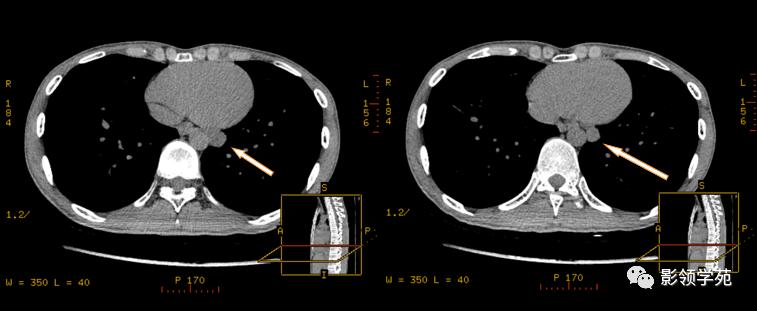

融合呈团的淋巴结中央见片状坏死